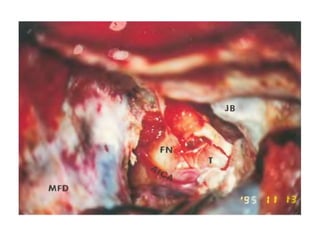

Fig. 9.21 To obtain control over the vascular structures as they enter

the temporal bone, the tympanic bone (TB), the fallopian canal remnants

(FC), and the infralabyrinthine air cells are all to be removed.

C Basal turn of the cochlea (promontory), IJV Internal jugular vein,

JB Jugular bulb, SS Sigmoid sinus

The view after completely uncovering the lateral surfaces of

the vascular structures. C Basal turn of the cochlea (promontory), ICA

Internal

carotid artery, IJV Internal jugular vein, JB Jugular bulb, SS Sigmoid

sinus

Fig. 9.29 The plane of dissection between the internal carotid artery

(ICA) and the overlying periosteum (P) is best developed at the entrance

of the artery into its canal. C Basal turn of the cochlea (promontory)